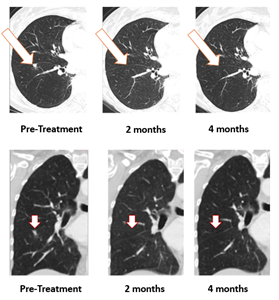

BriaCell Confirms 100% Resolution of Lung Metastasis with Bria-OTS™